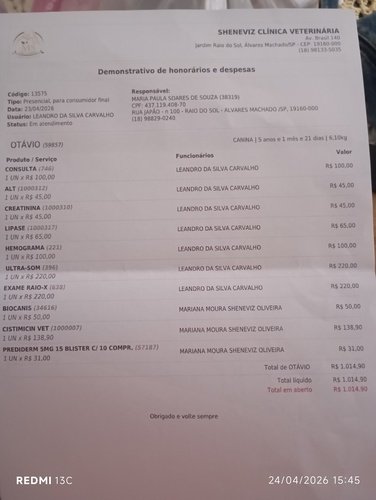

Olá pessoal, eu sou o Otávio tenho 6 aninhos, fui achado em uma estrada de sítio abandonado, fui resgatado , não encontrado dono e acabei sendo adotado. Comecei a andar curvado, de não conseguir andar, barriga bem distendida e fui levado ao veterinário, porém foi feito vários exames e deu fezes retidas a ponto da dor ser intensa e não andar, também infecção de urina, o tratamento ficou caro e peço a ajuda de vocês com qualquer quantia que tocar no seu coração. Agradeço imensamente.